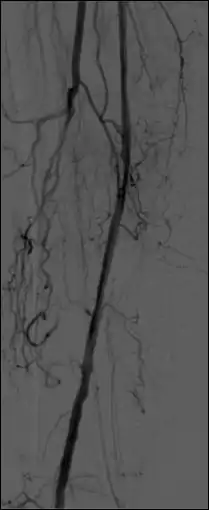

- The temporal-averaging feature of digital noise reduction can also be used for image presentation purposes so that the time course of the movement of contrast medium during a study can be displayed using just one image - see an example in Figure 7.4 from the peripheral study shown above - instead of a sequence of numerous images. Such an image is sometimes referred to as a Vascular Trace.

- One method of temporal filtration, referred to as Integrated Mask-Mode DSA involves adding (also called integrating) a number of images, acquired prior to the arrival of the contrast medium, to form an integrated mask image and adding a number of peak-opacification images to form an integrated live image. This is the process that was used to generate the vascular trace image in Figure 7.4. Thus, when four images are used to generate each integrated mask and live images, eight of the 25 images are now used in the subtraction process and, as a result, only 68% of the dose is wasted, and a subtraction image with lower noise results.

- A second method of temporal filtration, referred to as Matched Filtration, attempts to utilise all 25 images. It involves using information derived from the temporal variation in the concentration of contrast medium in the blood vessel of interest. This information can be obtained by using densitometric analysis software to plot the dilution curve for a region of the blood vessel, i.e. a plot of the time course of the contrast medium. This dilution curve is then used to define a range of weighting factors that are applied to each image in the sequence and the resulting images are simply added together. The processed DSA image has a relatively high SNR as a result of the integration of images. Further refinement of such filters can be used to colour-code parameters such as the time-of-arrival and the time-to-peak opacification, into the displayed image data. Although Matched Filtration has been shown both theoretically and experimentally to generate a DSA imaging process with good image quality and dose utilisation characteristics[27], it has not gained widespread clinical application.

- Additional processes involve Bolus Chasing, Rotational Angiography and Volume Tomographic Angiography. Bolus Chasing[28] has been found to be particularly helpful in peripheral angiography, for example. Here, the progress of the contrast medium is tracked automatically and used to increment the table and/or XRT/image receptor movement to the next anatomical region. The subsequent set of subtraction images can then be used to construct a composite image of the peripheral vasculature. In Rotational Angiography[29], a C-arm assembly, for example, can be caused to rotate at 10 - 30 degrees per second during the imaging sequence. Subsequent dynamic display of the subtraction images can be used to generate a perceived 3D presentation so that complex relationships within the vasculature can be more readily appreciated. Volume Tomographic Angiography[30] is similar to Computed Tomography (CT) where the C-arm is rotated around the patient during the imaging sequence. The image data is subject to a volume reconstruction algorithm which permits generation of three-dimensional images of the opacified vasculature. We will consider this latter process in more detail below.